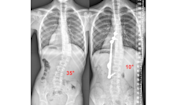

Degree Scoliosis Cervical Curve